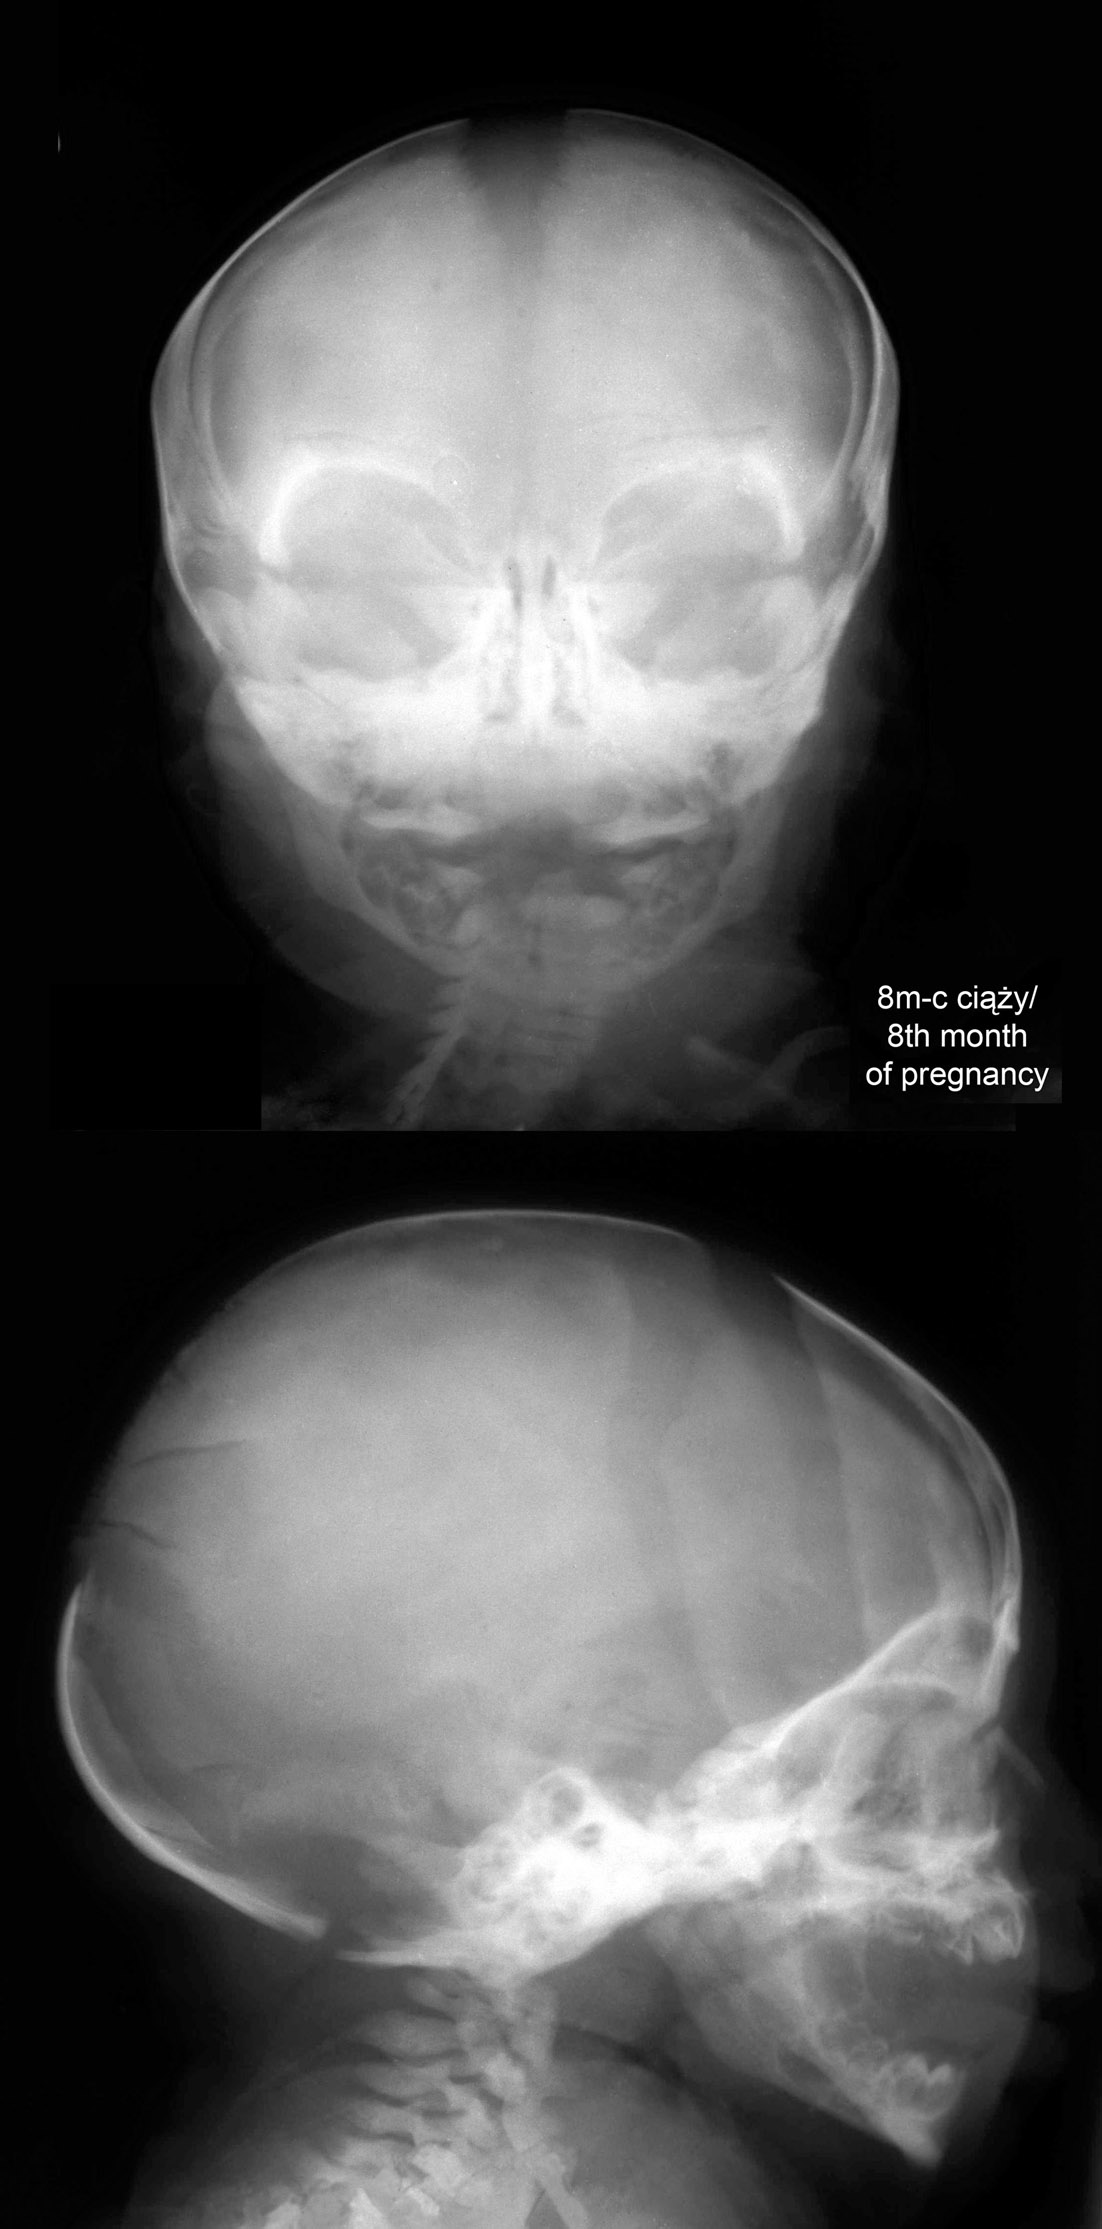

Radiografia / Radiography

RTG głowy płodu w 8 m-cu ciąży.